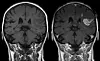

Ødelagt blod-hjernebarriere etter hjerneslag, vist på MRI.